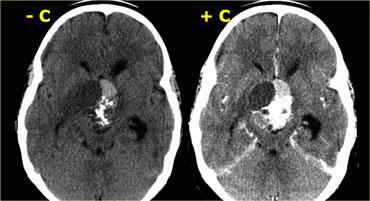

Phình động mạch và U màng não

Một trong những chẩn đoán phân biệt khó nhất trên CT là phình động mạch so với u màng não.

Ở bệnh nhân này có một khối lớn ở bên phải, có thể xuất phát từ màng não hoặc xoang hang.

Trên CT, không thể phân biệt được liệu khối này là túi phình động mạch hay u màng não.

Đây là hình ảnh MRI của cùng bệnh nhân.

Khối có tín hiệu chủ yếu là đen và có một xảo ảnh dòng chảy lớn chạy theo hướng mã hóa pha.

Các đặc điểm này tương ứng với dòng máu chảy nhanh, do đó khối này phải là một túi phình động mạch.

Hình chụp mạch máu của cùng bệnh nhân.

Hình ảnh cho thấy dòng chảy trong túi phình không phải là dòng chảy tầng (laminar), mà là dòng chảy xoáy, lấp đầy dần lòng túi phình bằng thuốc cản quang.